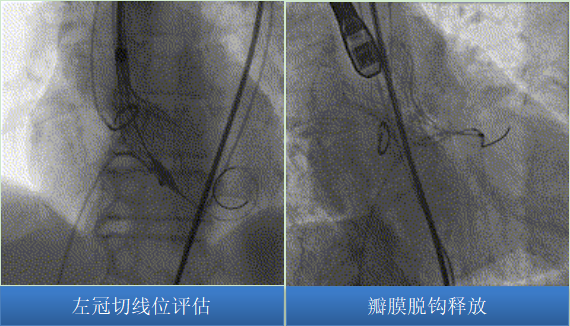

圖片

依據(jù)CALM原則,予多角度評(píng)估瓣膜后,將瓣膜脫鉤釋放。

瓣膜釋放后流入端形態(tài)稍受限伴少中量反流,予以22mm球囊后擴(kuò)張瓣膜形態(tài)、位置良好,峰值壓差10mmHg,冠脈血流灌注正常,弓部造影未見異常。